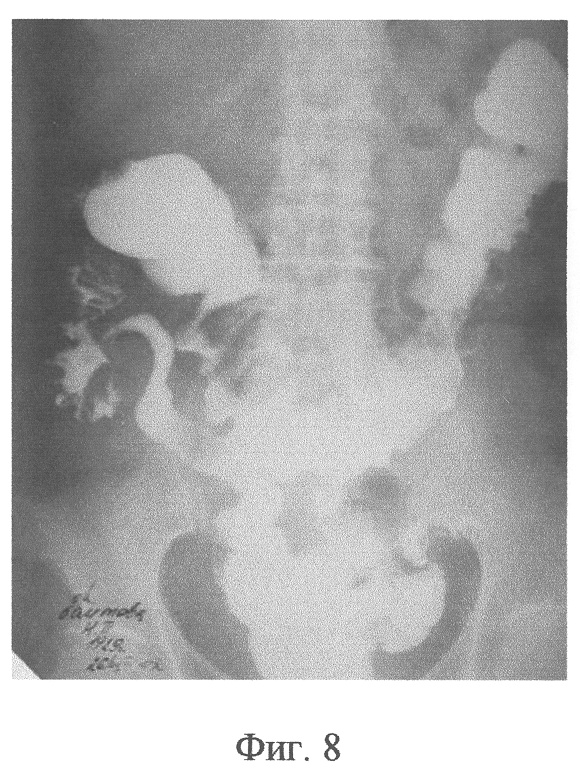

Фиг.8 – контрольная ирригограмма больной Б. после лечения; Т-образный толстокишечный анастомоз, состояние после закрытия колостомы.

На 10 сутки после операции компрессионные устройства из зоны образованного анастомоза самостоятельно отторглись и эвакуировались естественным путем, в результате чего сформировалось полноценное соустье (Фиг.6). Колостому на передней брюшной стенке через 16 суток закрыли внебрюшинным способом. После этого, на 9 сутки, больная выписана с хорошей функцией анастомоза (Фиг.7, 8).